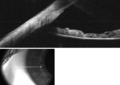

طريقة نسبة EZ

طريقة نسبة EZ هي إحدى الطرق لحساب عمق الغرفة الأمامية المقدر.[2] للبدء ، ينظر المريض إلى هدف على مسافة مع تغطية عين واحدة. يلتقط الفاحص صورة رقمية للعين المفتوحة المفحوصة ، من الجانب ، بشكل عمودي على المحور البصري (صورة الملف الشخصي). .

يجب بعد ذلك قياس المتثابتات التالية في الصورة ، باستخدام حاسوب شخصي أو هاتف ذكي (الأشكال 1،2):

1. مسافة البكسل بين الحوف (ملتقى القرنية الصافية والصلبة البيضاء) ومقدمة القرنية . يشار إلى هذه المسافة باسم Z.

2. مسافة البكسل بين الحوف ومركز الحدقة . يشار إلى هذه المسافة باسم E.

نسبة E: Z هي النسبة الحسابية بين E و Z.

ترتبط هذه النسبة خطيًا بعمق الغرفة الأمامية بالمعادلة التالية:

عمق الغرفة الأمامية (معبراً عنه بالمليمترات) = -3.3 × نسبة EZ + 4.2

وقد ثبت أن هذا التقدير دقيق مع مدي ثقة 95٪ +/- 0.33 مم خطأ ، بالمقارنة مع قياسات عمق الغرفة الأمامية بواسطة تصوير شيمبفلنج .[2]